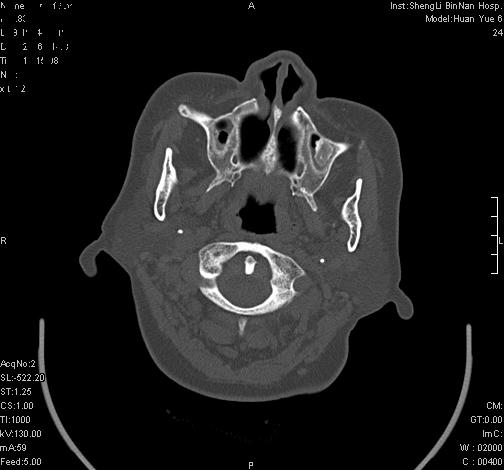

上次发的片子,不够细微。误导了大家,请大家再重新看一下,思路会更清晰。

双侧上颌窦上部黏膜明显增厚、窦腔缩小,偏后侧窦壁骨质毛糙、模糊,窦腔内见条块状钙化。结合双侧鼻甲黏膜明显增厚,以及临床症状,

考虑:双侧上颌窦霉菌性鼻窦炎

双侧上颌窦密度增高,粘膜增厚,内见条片状钙化,窦壁无增生与破坏征象,双侧鼻甲粘膜肥厚.

意见:双侧霉菌性上颌窦炎.

温习:真菌性鼻旁窦ct特征 1)非侵袭性病变者可涉及到鼻腔和鼻窦,多为单侧,上颌窦最多见.2)ct示窦腔内软组织增生影,可呈息肉状,+c可强化3)增生软组织影内可见散在斑片状或沙砾状钙化区,此为其典型特点,4)

非侵袭性病变可见窦壁骨质增生,破坏少见;侵袭性病变可见窦壁骨质破坏.